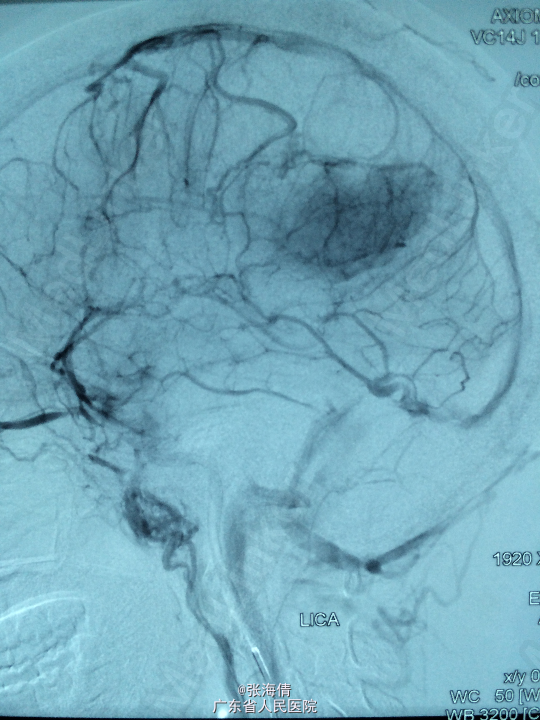

主诉:头晕、恶心6h 病史:患者男,22岁,2年来头晕、恶心症状多次出现,发作频率无明显规律,每次约2 min,无其他不适。6小时前上述症状加重,伴呕吐,呕吐物为胃内容物,外院CT平扫:示右侧颞顶叶见结节状稍高密度影,外院MR提示:平扫示右颞顶叶可见结节状稍长T1混杂T2信号影,大小约2.5 cm×2.1 cm×2.6 cm,边界较清晰,周围见长T1长T2水肿信号,SWI序列病变内未见明显低信号,DWI示信号稍高,增强扫描明显均匀强化,可见分叶,右侧脑室后角轻度受压

查体:全身未触及明显肿大淋巴结。脑膜刺激征:颈项强直,Kernig’S征阳性。 辅助检查:外院CT平扫:示右侧颞顶叶见结节状稍高密度影,外院MR提示:平扫示右颞顶叶可见结节状稍长T1混杂T2信号影,大小约2.5 cm×2.1 cm×2.6 cm,边界较清晰,周围见长T1长T2水肿信号,SWI序列病变内未见明显低信号,DWI示信号稍高,增强扫描明显均匀强化,可见分叶,右侧脑室后角轻度受压

诊断:脑膜瘤 处理:先予DSA以明确肿瘤供血情况,术中脑膜瘤供血丰富,用PVA颗粒超选到供血动脉将其闭塞。后再择期在气管全麻下行脑膜瘤切除术。

术后病理提示:脑膜瘤,WHO I级,瘤组织浸润脑组织。免疫组化:Ki一67(<1%)(+),CK(一),GFAP(一),Vimentin(+),EMA(+),P53(一),ER(一),PR(一)。 讨论:脑膜瘤首选方法为手术切除,手术切除脑膜瘤是最有效的治疗手段,但是由于其供血经常较为丰富,故可先行介入栓塞供血动脉后再行切除,这样可以降低手术风险和手术难度,改善患者手术预后。